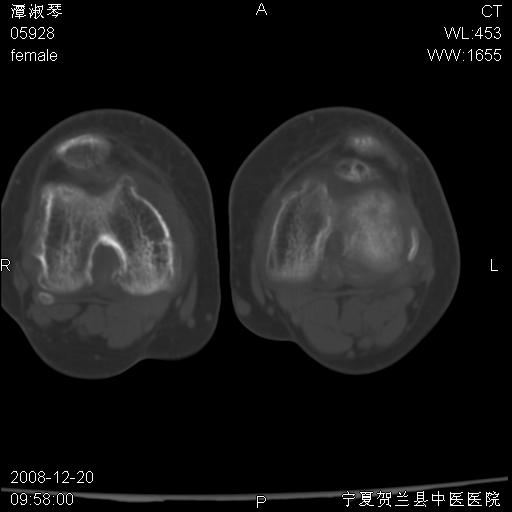

标题: CT17526:请各位看看是啥?

内生软骨瘤?骨梗死?

考虑内生软骨瘤可能性大

考虑-----骨梗死+退变

支持骨梗死,退行性骨关节病,膝关节积液.

考虑骨梗死可能性大

骨梗死可能性大

左股骨下段骨梗死。双膝退变。

左胫骨下端松质骨及髓腔内可见点片状高密度灶,骨皮质无明显膨胀及变薄。病变范围较长。支持骨梗死,退行性骨关节病,膝关节积液